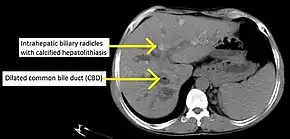

| Cholangiogram of primary sclerosing cholangitis. | |

Historically, a cholangiogram would be obtained via endoscopic retrograde cholangiopancreatography (ERCP), which typically reveals "beading" (alternating strictures and dilation) of the bile ducts inside and/or outside the liver. Currently, the preferred option for diagnostic cholangiography, given its non-invasive yet highly accurate nature, is magnetic resonance cholangiopancreatography (MRCP), a magnetic resonance imaging technique. MRCP has unique strengths, including high spatial resolution, and can even be used to visualize the biliary tract of small animal models of PSC.[18]